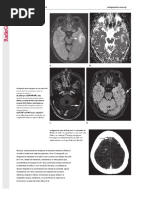

BI-RADS 5.

Proyeccin oblicua medio lateral.

BIRADS 5: Altamente sugestiva de malignidad. Ms de 95% de posibilidad de cncer. Se recomienda tomar acciones apropiadas. (Biopsia). En este caso: radiopacidad = densidad de bordes irregulares y espiculados que retrae el pezn.

The radiology assistant (2007) BI- RADS . Recuperado el 7 de noviembre del 2007. Web: http://www.radiologyassistant.nl/en/4349108442109